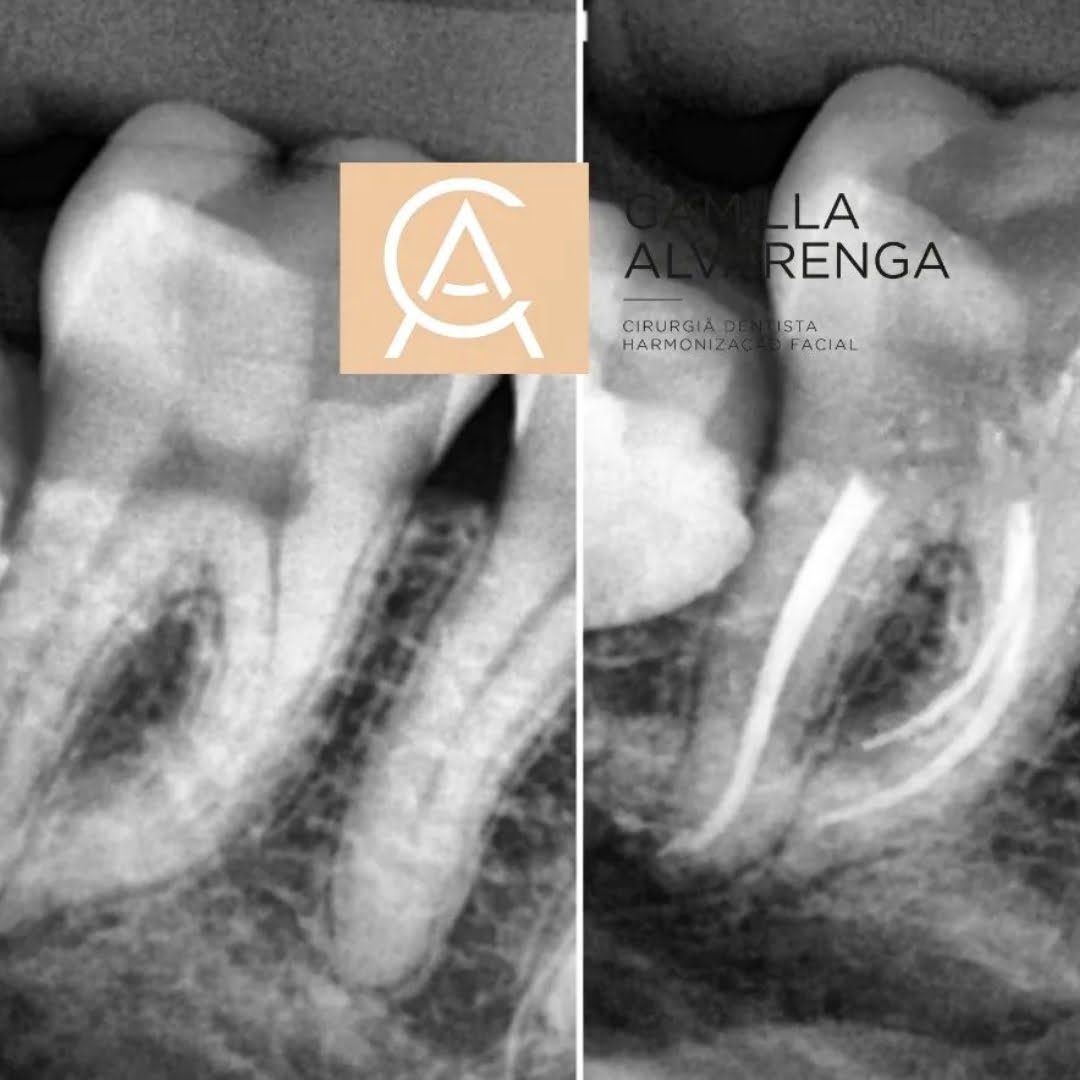

A Endodontia, mais conhecida como Canal, é um tratamento para dentes danificados por uma grande cavidade. A Endodontia é indicada quando a polpa dentro do canal radicular fica inflamada e infectada.

O procedimento funciona criando um pequeno orifício no dente para que todas as áreas infectadas possam ser removidas. A polpa dentária é removida e, muitas vezes, para prevenir a propagação da infecção, as raízes também são removidas.

Uma vez feito isso, a área é limpa para garantir que a infecção tenha desaparecido. Normalmente antibióticos são prescritos. Isso garante que qualquer infecção persistente seja eliminada.

Para um diagnóstico preciso e acompanhamento da evolução do seu tratamento.